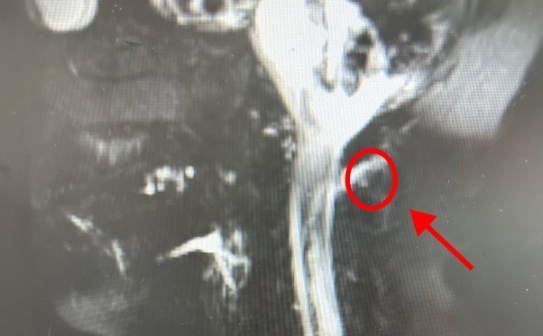

疼痛科副主任医师李庆华认为,林大姐的症状疑似低颅压性头痛。经检查,其颈椎处有明显的漏液 。医生表示“是脑脊液漏出导致的低颅压性头痛,且破口位置较高,在颈椎处。”

图源:健康杭州

“临床上,低颅压患者脊椎相应的漏液部分,经常会发现骨刺。”李庆华表示这与生活习惯有很大的关系,低头族要特别当心。